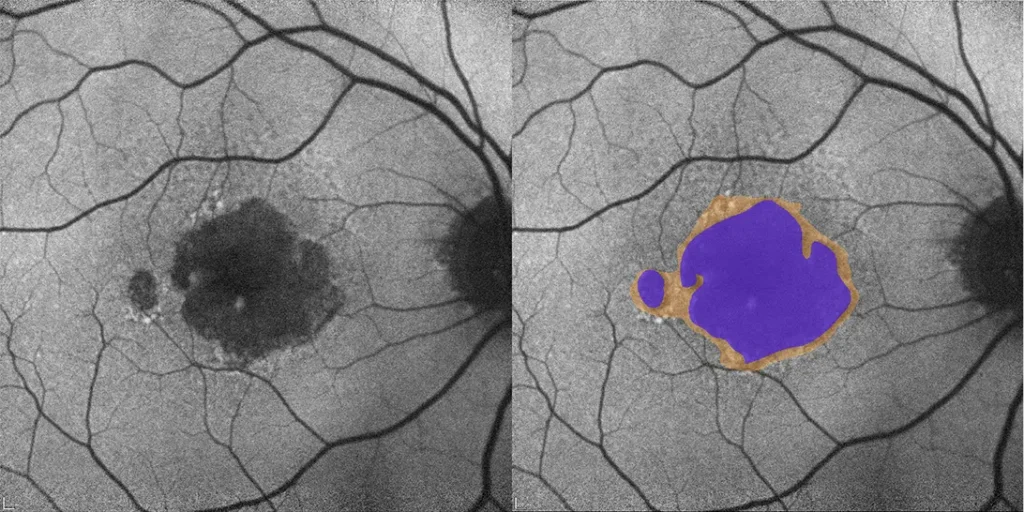

- Geographic Atrophy (GA) Segmentation and Quantification

- Ellipsoid Zone (EZ) Thickness and Loss Area

- En Face Measurements

- Fluid Segmentation with Linear, Area, and Volume Quantification:

- Intraretinal Fluid (IRF)

- Subretinal Fluid (SRF)

- Pigment Epithelial Detachment (PED)

- Subretinal Hyper-Reflective Material (SHRM)

- Drusen Quantification

- Hyper-Transmission Defect Detection/Quantification

- Progression Tracking

- Multimodal Overlay

Our multimodal overlays combine structural and functional imaging modalities, such as OCT, FAF, and microperimetry, to provide a more comprehensive understanding supported by expert-trained readers who interpret across modalities with deep disease insight.